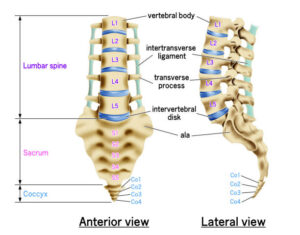

La lumbalgia aguda es un dolor de gran intensidad ubicado en la zona baja de la espalda que llega a aparecer de manera súbita, por lo general, tras un esfuerzo físico, una mala postura o un movimiento brusco, pero no todo dolor de espalda es exactamente igual.

- Dolor “en cinturón”: que se corre hacia las nalgas o piernas.

En nuestra Clínica InDolore, nuestro enfoque como especialistas en tratamiento del dolor en Puebla es llevar a cabo un diagnóstico diferencial de gran precisión. Esto quiere decir que llegamos a reconocer si el dolor es puramente muscular o si existe una compresión nerviosa, como en el caso de una estenosis o una hernia discal que necesita una intervención más avanzada.